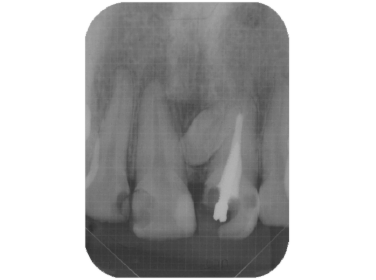

- 前歯の違和感を主訴に来院した症例(写真をクリックして下さい)

- 歯内療法の不備から上顎洞にまで炎症が波及してしまった症例

初診時のレントゲン写真

写真の右から2本目の歯の違和感でいらっしゃいました。

CT撮影すると、炎症は上顎洞にも波及しています

このように、通常のレントゲンだけでは炎症による病変の範囲等がわかり難い場合はCT撮影も行います。